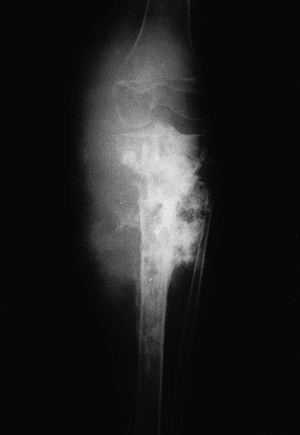

En la primera radiografía, anteroposterior y lateral de pierna derecha (fig. 1), se aprecia una importante área de aumento de densidad en el tercio superior de la tibia ocupando la metáfisis tibial y la zona más proximal de la diáfisis. La epífisis queda respetada pues el cartílago metafisario parece, en este momento, actuar de barrera natural para evitar la progresión en esa dirección de la lesión. Además se observa una masa osificada de partes blandas adyacentes y una reacción perióstica netamente maligna como estímulo de desarrollo perióstico, el llamado triángulo de Codman.